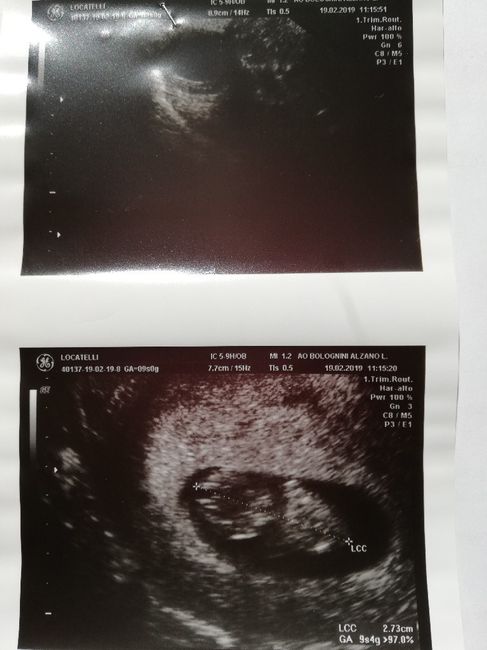

Ciao a tutte mamme e future mamme! Qualcuna conosce il metodo Ramzi? Ho fatto eco interna ieri a 7+3, procede tutto bene e ora sono curiosa di sapere cosa potrebbe essere il mio fagiolino! ❤ grazie a chi mi risponderà